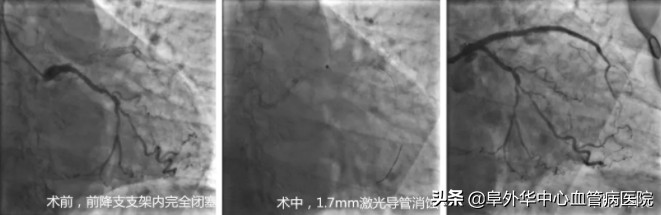

确实,张女士的病情比较复杂:入院后行冠脉造影,发现张女士前降支支架内完全闭塞。此前张女士反复出现支架内再狭窄,在不同医院先后尝试过切割球囊、药物球囊扩张、强化药物治疗等多种治疗方法,但疗效不理想。

闫继锋主任、闫瑞主治医师走上手术台,采用1.7mm激光导管,释放能量40mJ/mm2、频率40Hz,对支架内斑块进行了2次消蚀。

接下来,球囊顺利通过病变部位,切割球囊、高压球囊、药物球囊完成扩张。应用光学相干断层成像(OCT)评估手术后效果,发现令人非常满意。